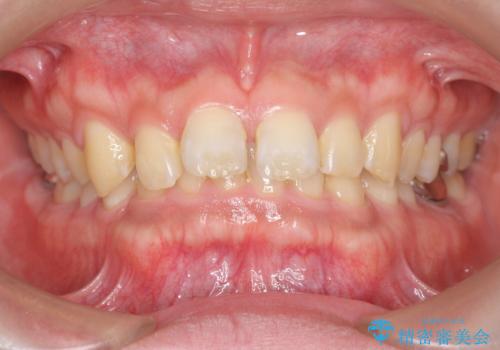

【モニター】デコボコ前歯を治したい ワイヤー装置での抜歯矯正治療

[ 社会人の矯正治療 ] 仕事をしながらでも治療しやすい、マウスピース矯正